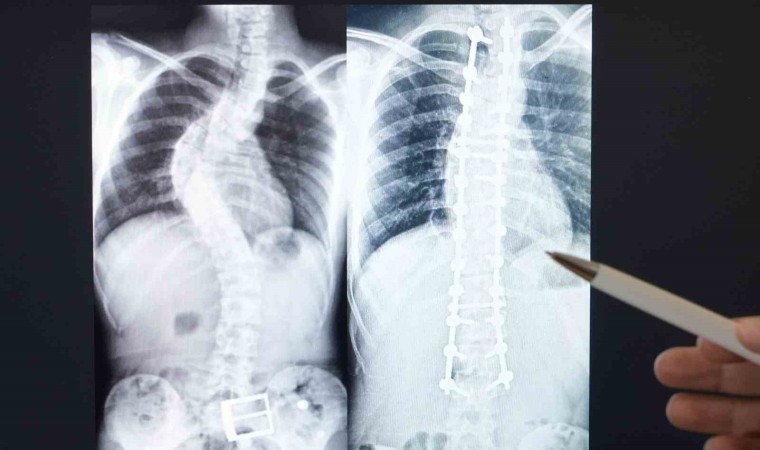

Memorial Antalya Hastanesi Ortopedi ve Travmatoloji Bölümü’nden Doç. Dr. Ömer Bozduman, skolyozun önden bakıldığı zaman omurganın eğriliğini ifade ettiğini belirterek, 10 derecenin üstünde çıktığı zaman skolyoz tanımını aldığını ifade etti. Genellikle hastaların duruş bozukluğu şeklinde hastaneye başvurduklarına dile getiren Bozduman, “Çekilen grafilerin de ölçüleri sonucunda belirli derecelerde skolyoz tanımı koyuluyor. Kız çocuklarında daha fazla görülür, doğumsalda olabilir, ileri yaşlarda kırık, enfeksiyon, tümör, kireçlenme gibi durumlarda da meydana gelebilir. Tedavisinde egzersiz, fizik tedavi, korse kullanılır. İleri yaşlarda cerrahi olarak tedavi yapılabilir” ifadelerine yer verdi.

En sık görülenin nedeni tam aydınlatılamayan skolyoz grubu olduğunu dile getiren Bozduman, “Bunlar ergenlik yaşındaki çocuklarda görülen ve cerrahiyle önüne geçilebilecek kısımdır. Anneler babalar ergenlikte çocuklarının mutlaka omuz, kalça dengelerini, belleriyle kolları arasındaki mesafenin simetrik olmasına dikkat etmelidir. Bu aşamada yakaladığımız birçok çocuğu ileride cerrahi ihtiyacı olmadan tedavi ve takip etme şansımız olabiliyor. Biraz daha büyük gruplarda, enfeksiyon, tümör, ramotolojik, sedromik hastalıklar nedeniyle omurgalarda eğrilik olabiliyor. Bazen çok ilerleyip komplikasyonlar oluşturabiliyor. Belirli bir derecenin üzerini ameliyat ediyoruz. Hastaya daha uzun ve kaliteli bir yaşam sağlamak ve derecesinin ilerlemesini engellemektir. Bazen de çok ileri yaşlarda kemik erimesi, kemik kırığı omurga eğriliği olabiliyor. Bunlara kanal darlıkları sinir sıkışması eşlik edebiliyor. Öncelikle kanal darlığı ve sinir sıkışmasını ortadan kaldırıp omurganın eğriliğini düzeltebiliyoruz” diye konuştu.

Bozduman, binde 3 ya da binde 7 arasındaki sıklıkta skolyozun görülebildiğini belirtti. Genelde 10 hastadan birine ameliyat ihtiyacı duyduğunu dile getiren Bozduman, “3’ünü takip, 6’sını fizik tedavi egzersiz korse ile takibe alıyoruz. Temel amacımız burada hataların ameliyat olmadan problemini çözebilmek. Eğer ki ameliyat ihtiyacı olacak şekilde derecesi ilerlediyse değerlendirip, hastanın ihtiyacı olan cerrahiyi fonksiyonlarını kaybetmemek kaydıyla öneriyoruz. Cerrahide hastanın önce bir genel değerlendirmesini yapıyoruz. Hastanın bu cerrahiye uygun olup olmadığına karar veriyoruz. Uygunsa genel anesteziyle açık bir cerrahi uyguluyoruz. Ameliyat sonrası yakın takibe devam ediyoruz. Hastamızı birkaç içinde taburcu ediyoruz ama yine düzenli kontrollerini yapıyoruz” ifadelerine yer verdi.